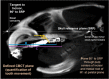

Orthodontic forces have been reported to significantly increase nicotine-induced periodontal bone loss. At present, however, it is unknown, which further (side) effects can be expected during orthodontic treatment at a nicotine exposure corresponding to that of an average European smoker. 63 male Fischer344 rats were randomized in three consecutive experiments of 21 animals each (A/B/C) to 3 experimental groups (7 rats, 1/2/3): (A) cone-beam-computed tomography (CBCT); (B) histology/serology; (C) reverse-transcription quantitative real-time polymerase chain reaction (RT-qPCR)/cotinine serology-(1) control; (2) orthodontic tooth movement (OTM) of the first and second upper left molar (NiTi closed coil spring, 0.25 N); (3) OTM with 1.89 mg·kg-1 per day s.c. of L(-)-nicotine. After 14 days of OTM, serum cotinine and IL-6 concentration as well as orthodontically induced inflammatory root resorption (OIIRR), osteoclast activity (histology), orthodontic tooth movement velocity (CBCT, within 14 and 28 days of OTM) and relative gene expression of known inflammatory and osteoclast markers were quantified in the dental-periodontal tissue (RT-qPCR). Animals exposed to nicotine showed significantly heightened serum cotinine and IL-6 levels corresponding to those of regular European smokers. Both the extent of root resorption, osteoclast activity, orthodontic tooth movement and gene expression of inflammatory and osteoclast markers were significantly increased compared to controls with and without OTM under the influence of nicotine. We conclude that apart from increased periodontal bone loss, a progression of dental root resorption and accelerated orthodontic tooth movement are to be anticipated during orthodontic therapy, if nicotine consumption is present. Thus patients should be informed about these risks and the necessity of nicotine abstinence during treatment.